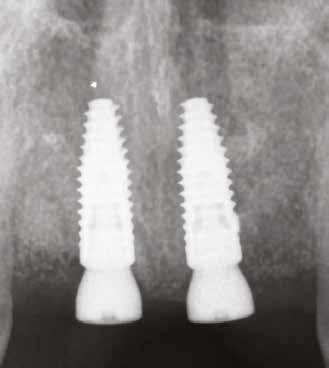

Két hónappal a fogeltávolítást követően készült egy újabb CBCT a felső állcsontról (7. ábra), illetve ismét vettünk egy digitális lenyomatot a DEXIS IS 3800 intraorális szkenner segítségével (8. ábra) . Ezek a lépések nélkülözhetetlenek az implantátumok helyének megtervezéséhez, illetve a sebészi sablon elkészítéséhez. A 3D szoftveres tervezés során az implantátumok pozícióinak meghatározása elsősorban a protetikai szempontok szerint történt (9–10. ábra). A sebészi fúrósablont is ennek megfelelően, egy sebészi sablonok tervezésére alkalmas szoftverrel terveztük meg és készítettük el (11. a–c ábra) . Mind a négy hiányzó fog területét megvizsgáltuk, majd kiválasztottuk azokat a legoptimálisabb és legjobban hozzáférhető területeket, ahova két implantátum és egy hídpótlás kerülhet. A tervezési fázist követően egy sebészi fúrósablont készíttettünk Stratasys 3D nyomtatóval, MED610 rezinből (Stratasys). Ezt követően behelyezésre került két implantátum (4,1 x 12,0 mm, Straumann Bone Level, Tapered, Regular CrossFit, SLActive, Roxolid), a precizitást a Straumann Guided Surgery szettje biztosította. A 2.1es fog gyökércsúcsa feletti csontban található amalgámdarabot óvatosan eltávolítottuk, egy apró szemcse maradt csupán az ínyben (12. ábra) . Az implantátumok

megfelelő gyógyulása és integrációja érdekében a bukkális csontot ismét augmentáltuk EthOss csontpótlóval, majd zártuk a sebet úgynevezett félig zárt (semi-submerged) technikával (13. a–b ábra)

A tízhetes gyógyulási idő leteltével ellenőriztük az implantátumok stabilitási hányadosát (ISQ). A következő lépés a végleges fogpótlás elkészítése, amelyet a páciens beküldő fogorvosa fog végezni. A csavarral rögzülő monolitikus hídpótláshoz a lenyomat intraorális szkennerrel készül, valamint a fogtechnikai lépéseknél is törekedni fognak a lehető legnagyobb mértékű digitalizálásra.